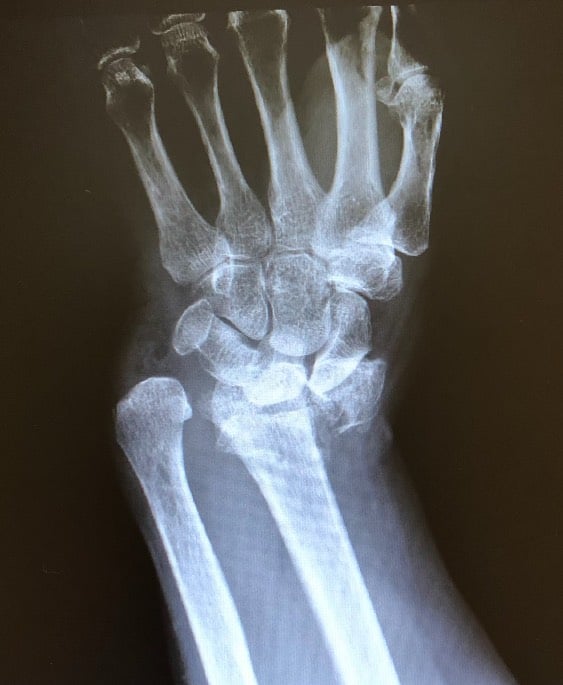

wrist broken xray

X-ray of Tami's broken wrist

“They were just very caregiving, focused, sympathetic and empathetic,” said Whiteside. She’d noticed that it was 9 p.m. when she arrived. Twenty minutes later, she’d been X-rayed and diagnosed with a broken radius, chipped ulna and a dislocated hand. An IV line with pain medication brought intense relief.